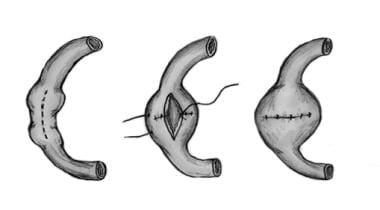

幽門形成術では、幽門括約筋の一部を切断して除去し、幽門を広げて弛緩させることが必要です。これにより、食物が十二指腸に通過しやすくなります。場合によっては、幽門括約筋が完全に除去されることもあります。

- 幽門括約筋の筋肉にいくつかの小さな切り込みを入れ、幽門の開口部を広げます。

- 幽門筋を下から上に縫い合わせます。